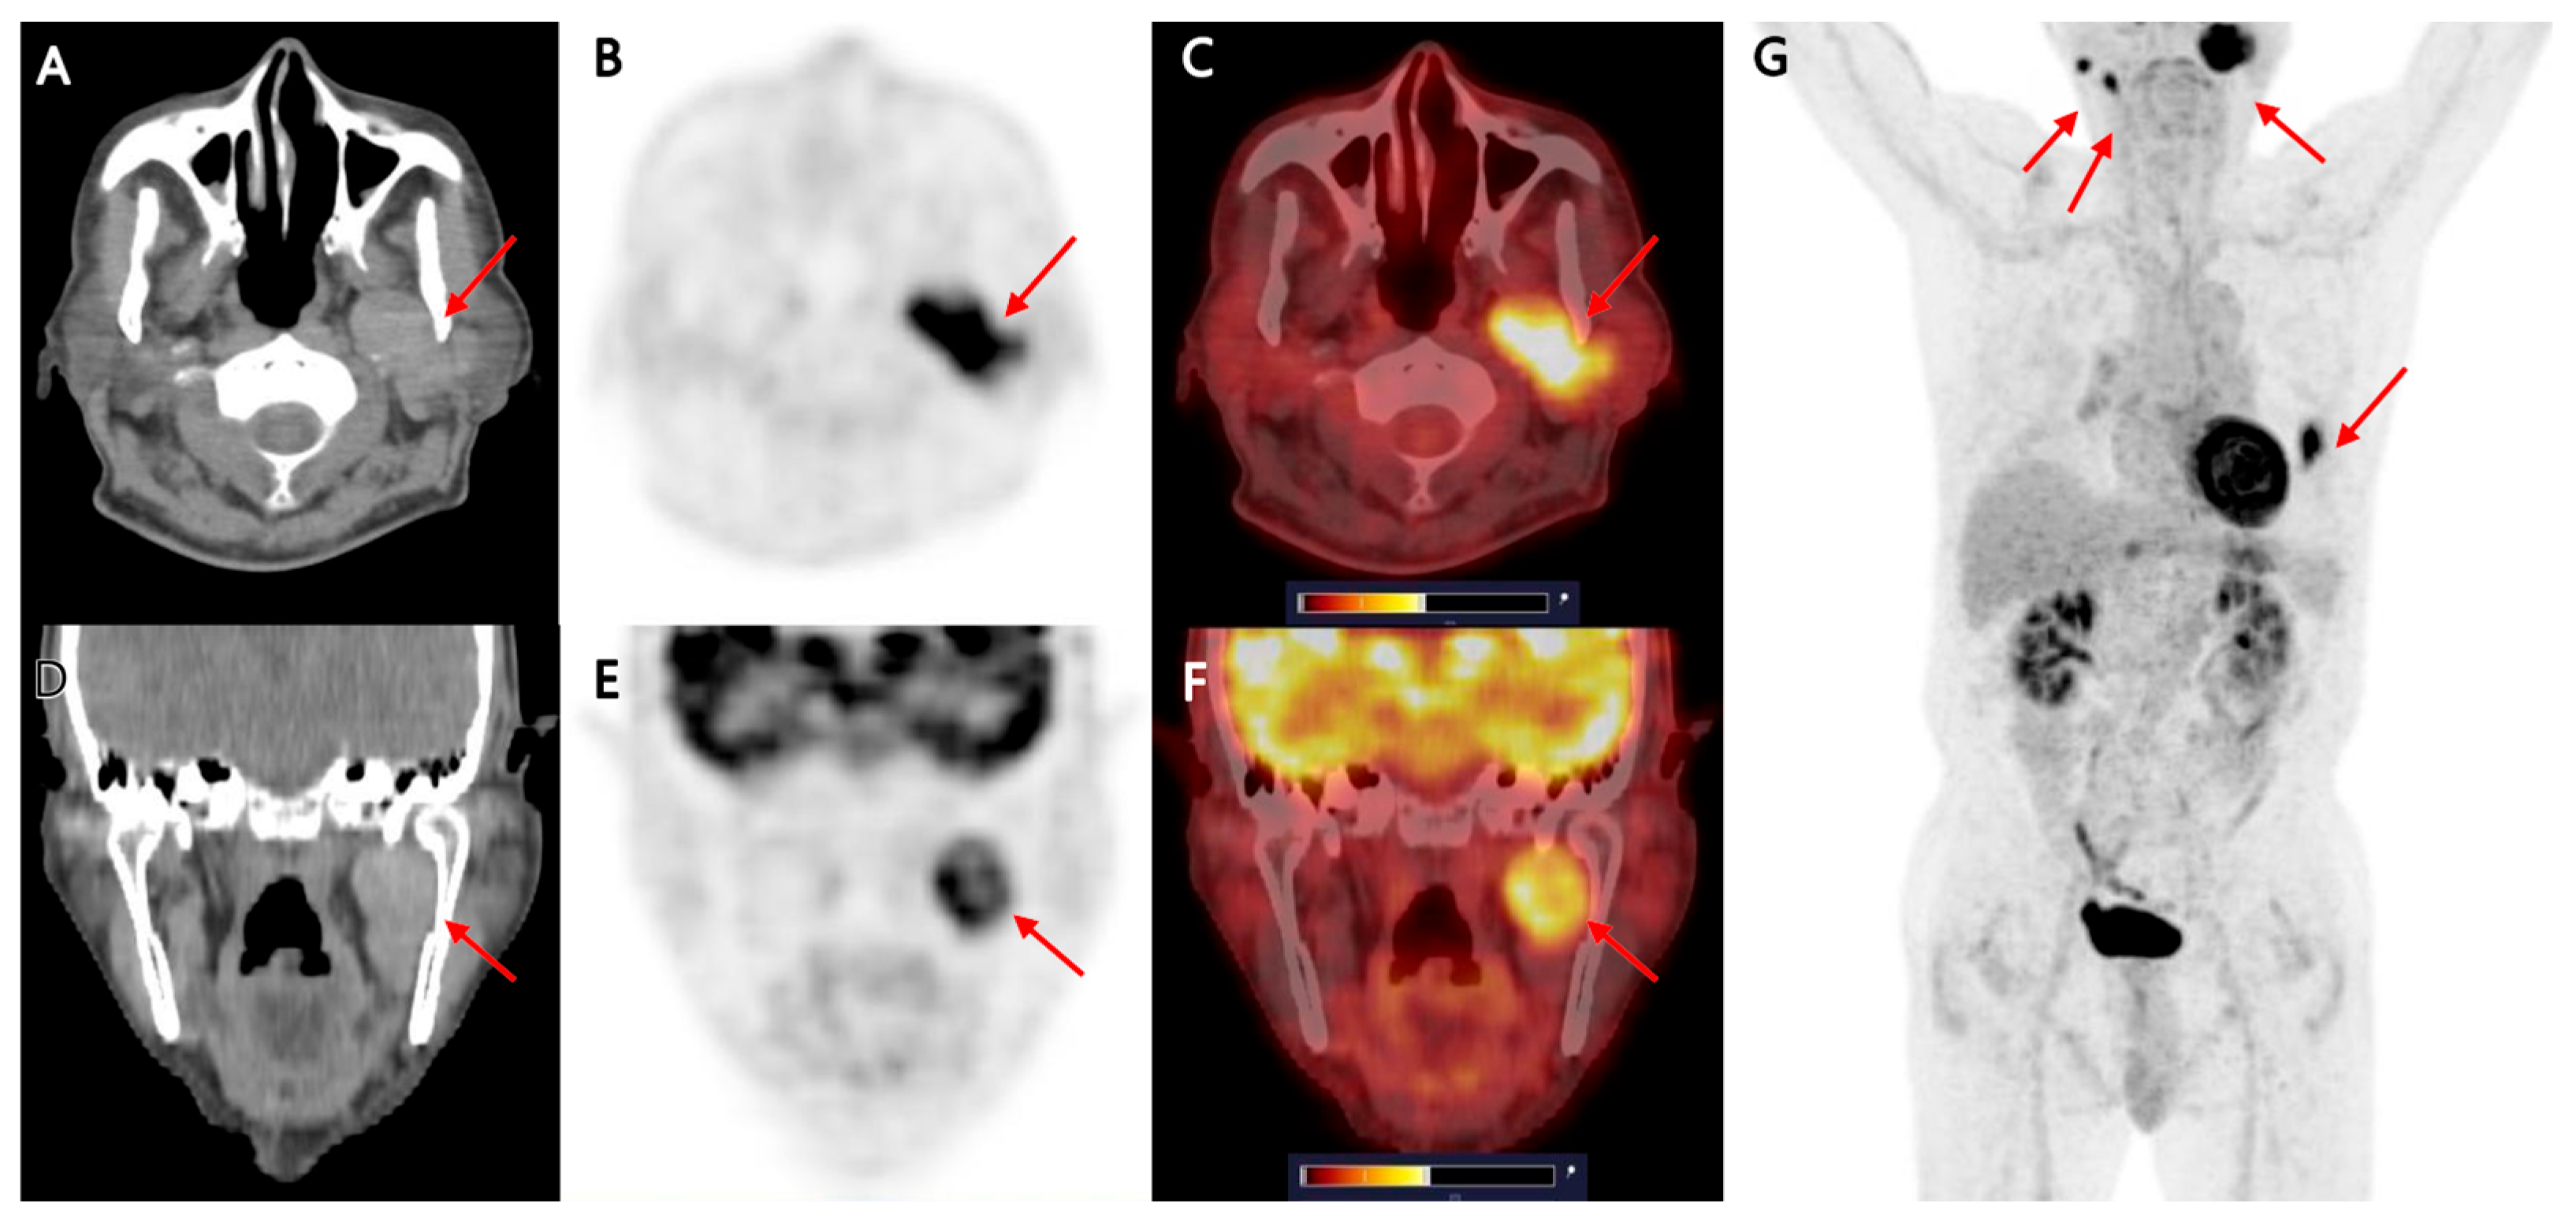

Multimodality Imaging of Warthin’s Tumor: PET/CT, Scintigraphy, MRI, and CT